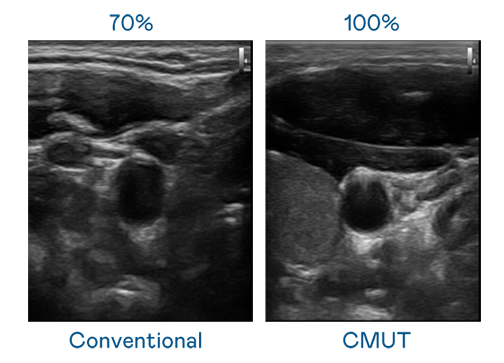

CMUT 技术是一种用电容式微机电元件来产生超音波讯号的技术。与传统 PZT 压电式技术相比,CMUT 频宽增加 30%,更宽频的超音波讯号让影像解析度大幅提升,是实现高影像品质医疗超音波扫描、促进精准医疗发展的关键技术。

大频宽带来超清晰影像

超音波影像的解析度高低,首先取决于探头能发出的讯号频宽。尊龙凯龙时官网进入网页 CMUT 可提供高清晰的超音波讯号,提供高频宽、高灵敏度、影像纹理细节更高的超音波影像,协助医护人员缩短影像判读时间及利用精准的医疗影像进行诊断。